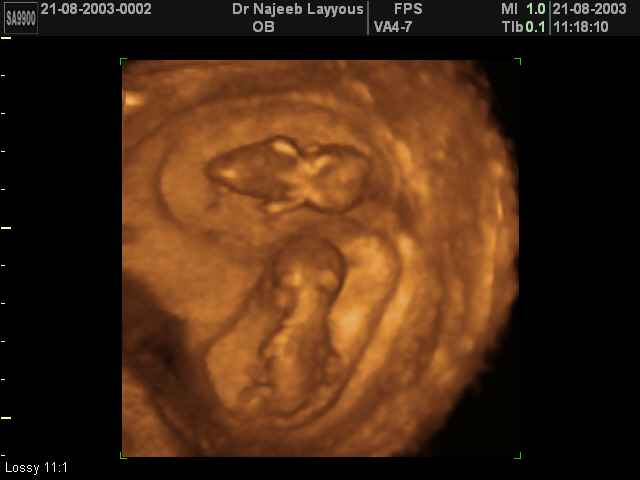

- لقطات فيديو للجنين بجهاز الموجات فوق صوتية رباعي الأبعاد

- صور للجنين في المراحل الأولى من الحمل

- صور لتوائم

صور لتوائم بجهاز الالتراساوند ثلاثي الأبعاد | الدكتور نجيب ليوس